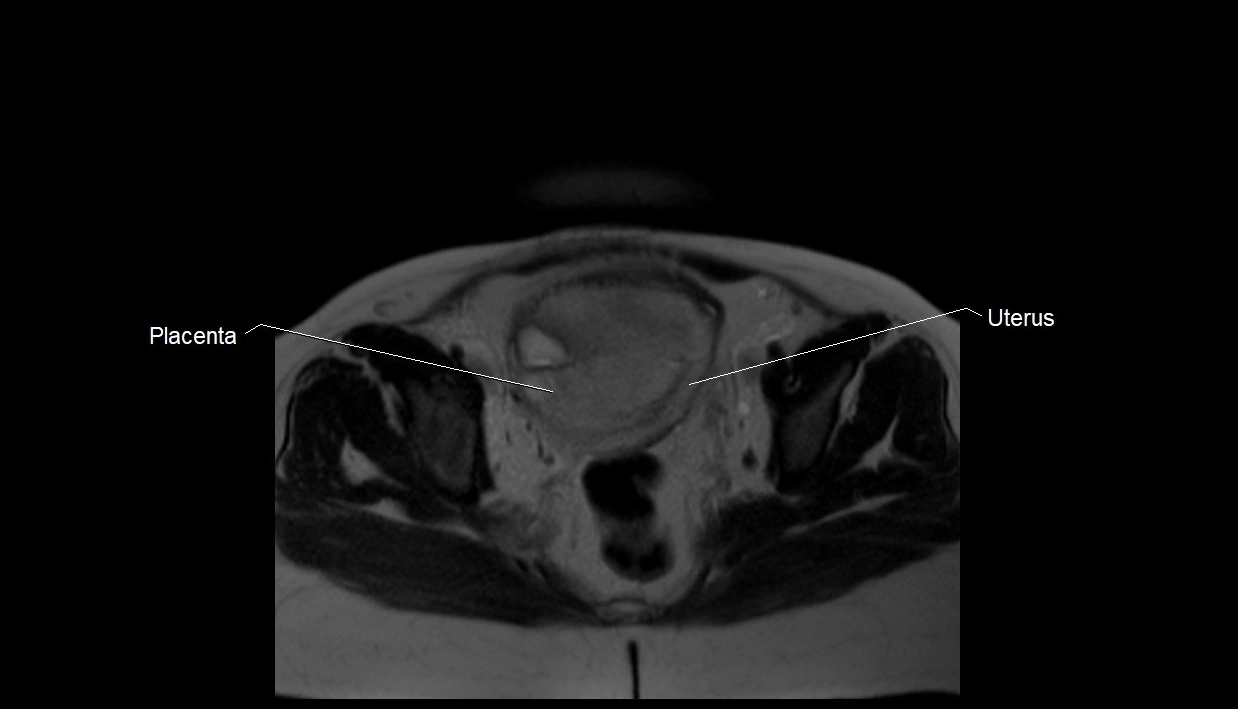

MRI Appearance

T2 HASTE (T2 GRE):

• Amniotic fluid shows very bright hyperintense signal

• Provides natural contrast against fetus and placenta

• Small particles (vernix) may appear as scattered hypointense foci within bright fluid